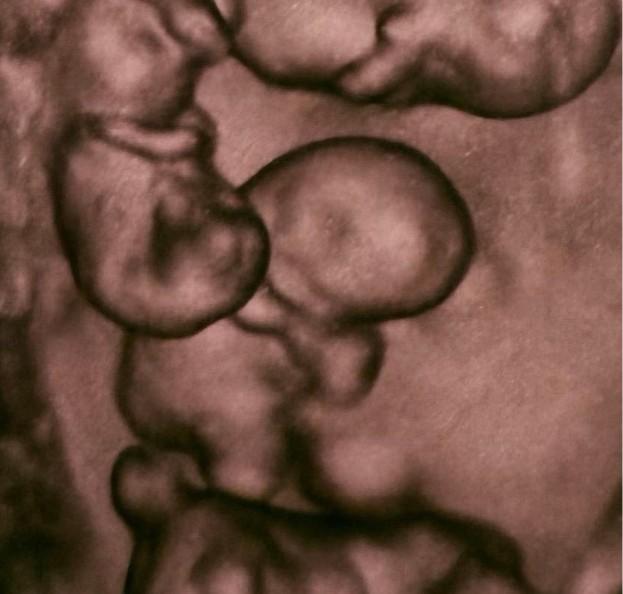

Что значит «монохориальная четверня»

фото:соцсети

Многоплодная беременность, во время которой происходит развитие двух и более эмбрионов, бывает двух видов: разнояйцевой (дизиготной) и однояйцевой (монозиготной). В обоих случаях она требует тщательного медицинского контроля и часто завершаясь кесаревым сечением.

Однояйцевая беременность — это развитие двух или более эмбрионов из одной оплодотворенной яйцеклетки (зиготы), которая разделилась на ранней стадии. Такие дети генетически идентичны: они всегда одного пола и внешне очень похожи. В большинстве случаев у них общая плацента.

По данным медиков, в мире известно всего около 15 случаев рождения четверняшек-близнецов, и в 10 из них рождались девочки.